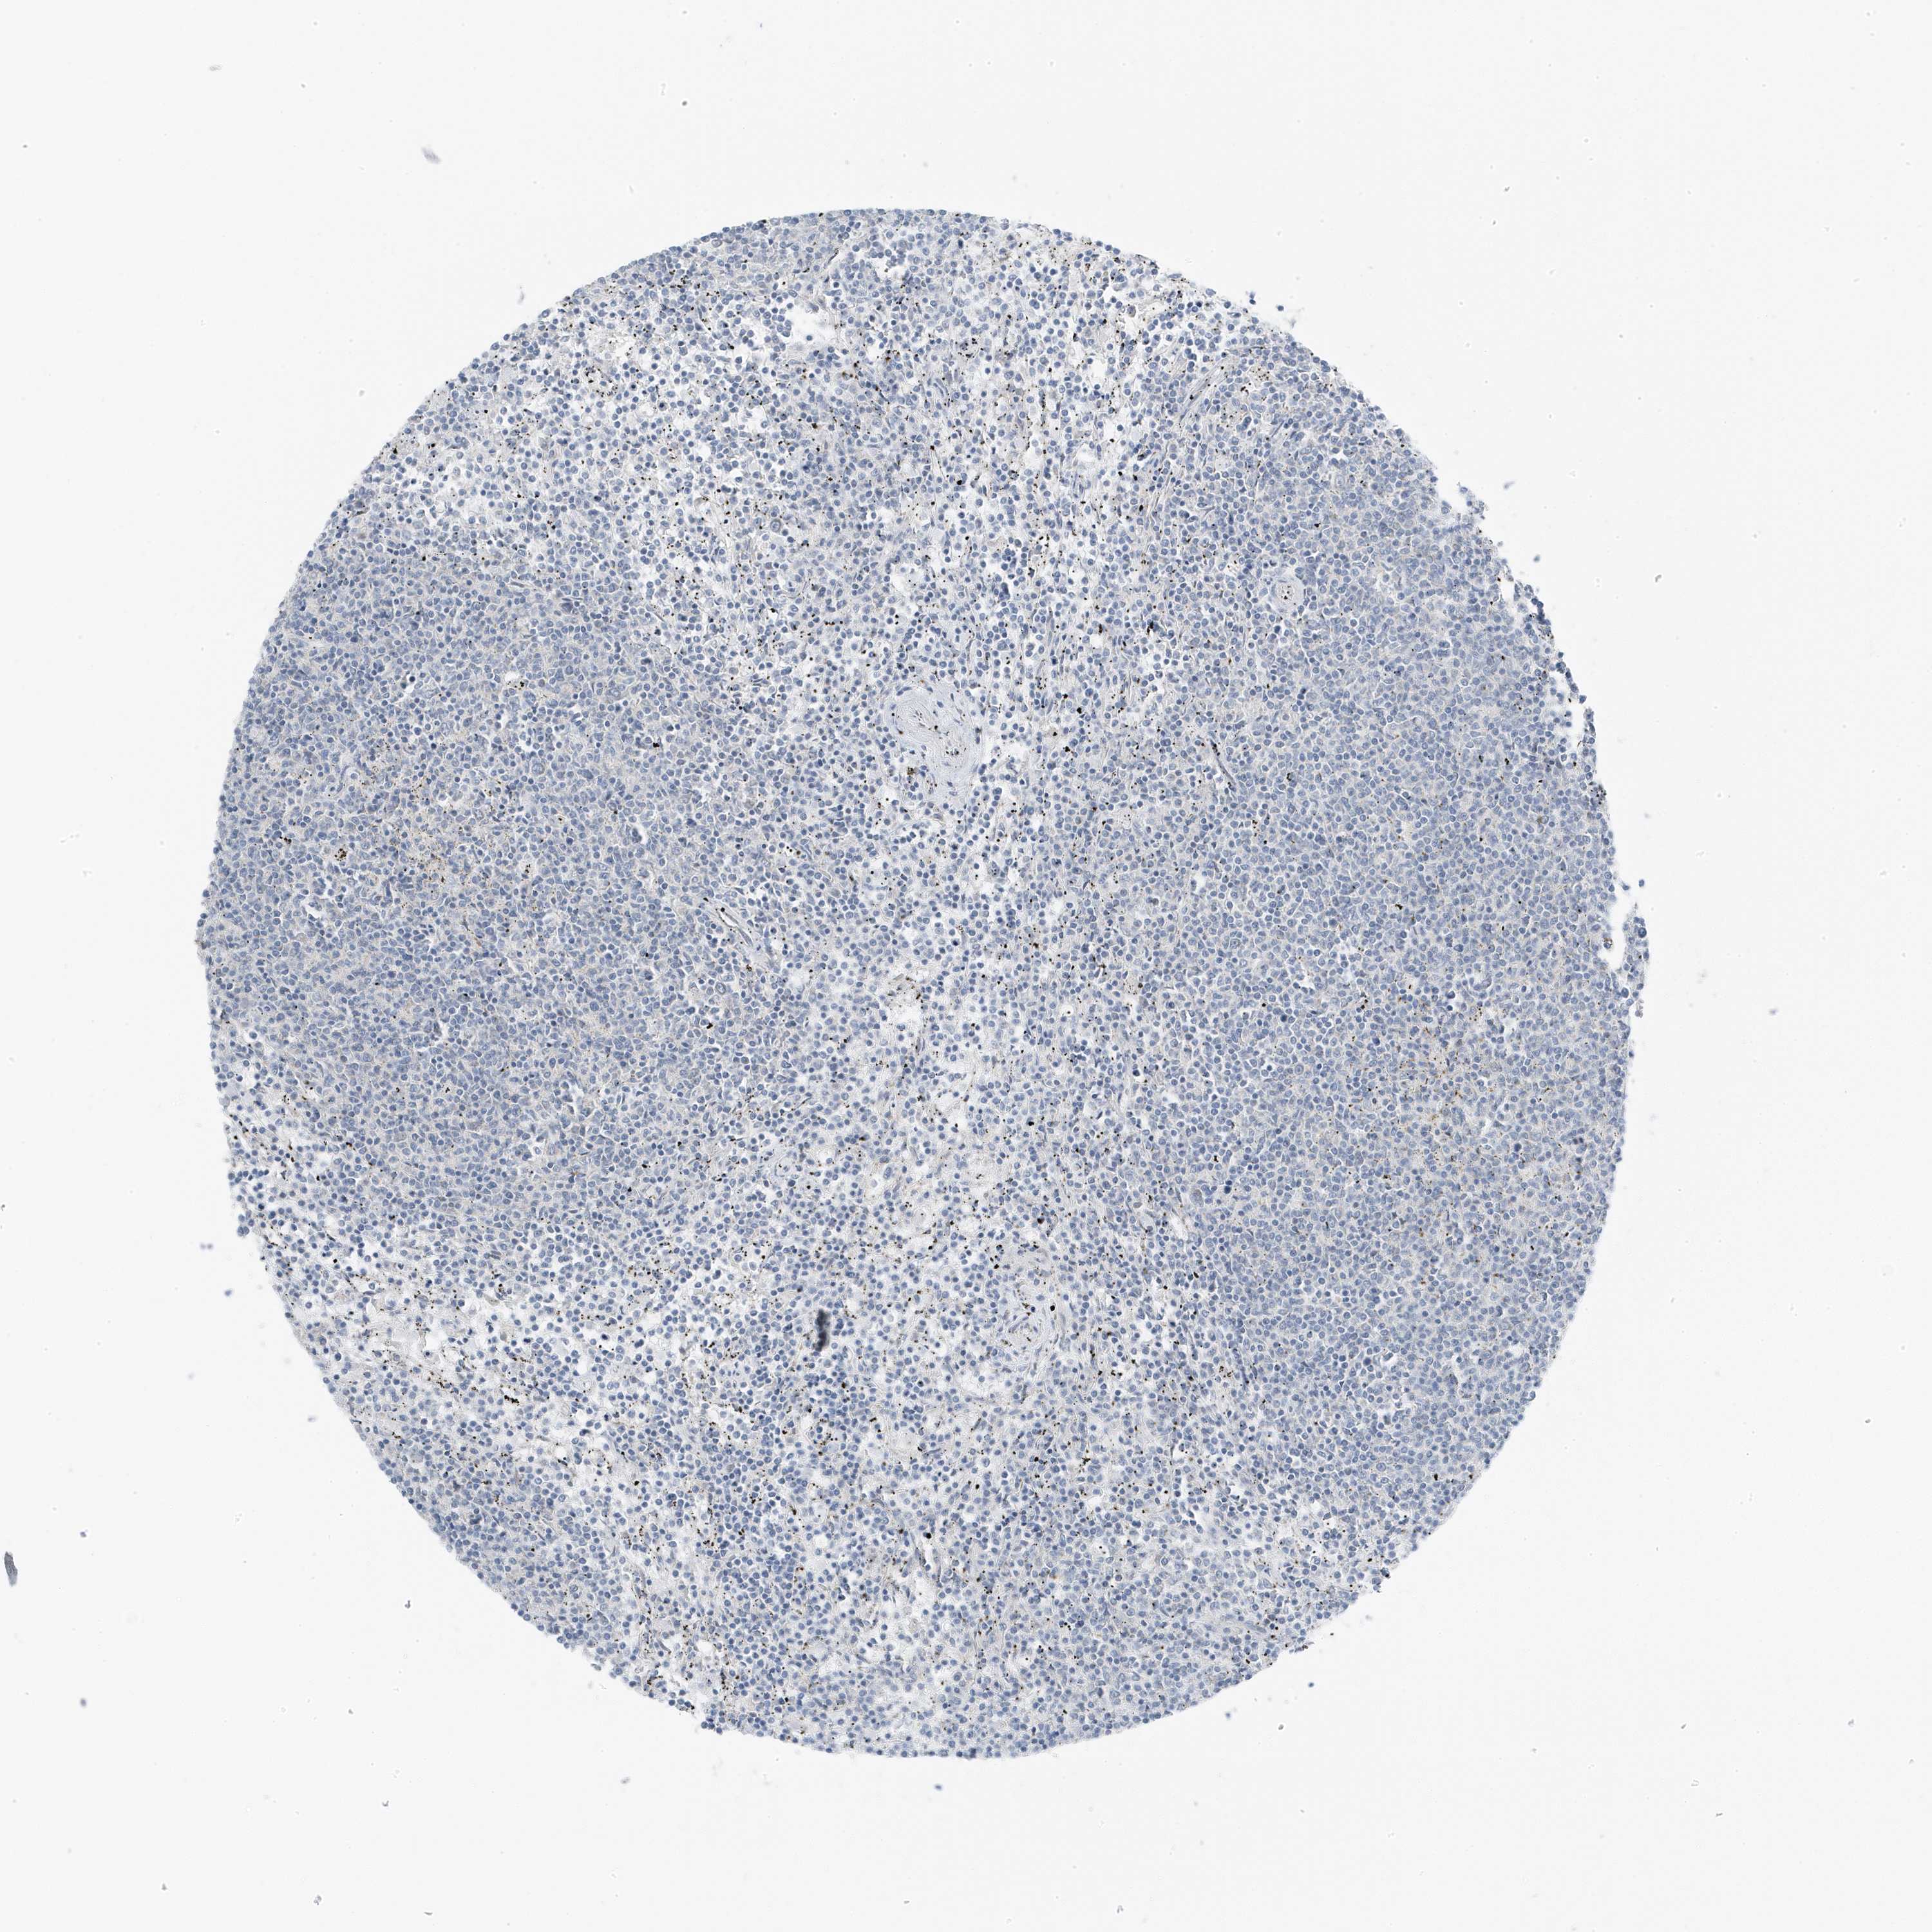

CANCER LYMPHOMA Show tissue menu

LYMPHOMA - Protein expressioni

A mouse-over function shows sample information and annotation data. Click on an image to view it in a full screen mode. Samples can be filtered based on level of antibody staining by selecting one or several of the following categories: high, medium, low and not detected. The assay and annotation is described here.

Each image is clickable and will lead to virtual microscopy that enables deeper exploration of all samples and also displays staining intensity scores, fraction scores and subcellular localization as well as patient and tissue information for each sample.

Antibody HPA029237

Staining

High

Medium

Low

Not detected

Intensity

Strong

Moderate

Weak

Negative

Quantity

>75%

75%-25%

<25%

None

Location

Nuclear

Cytoplasmic/membranous

Cytoplasmic/membranous,nuclear

Hodgkin's disease, NOS

Malignant lymphoma, non-Hodgkin's type, High grade

Malignant lymphoma, non-Hodgkin's type, Low grade